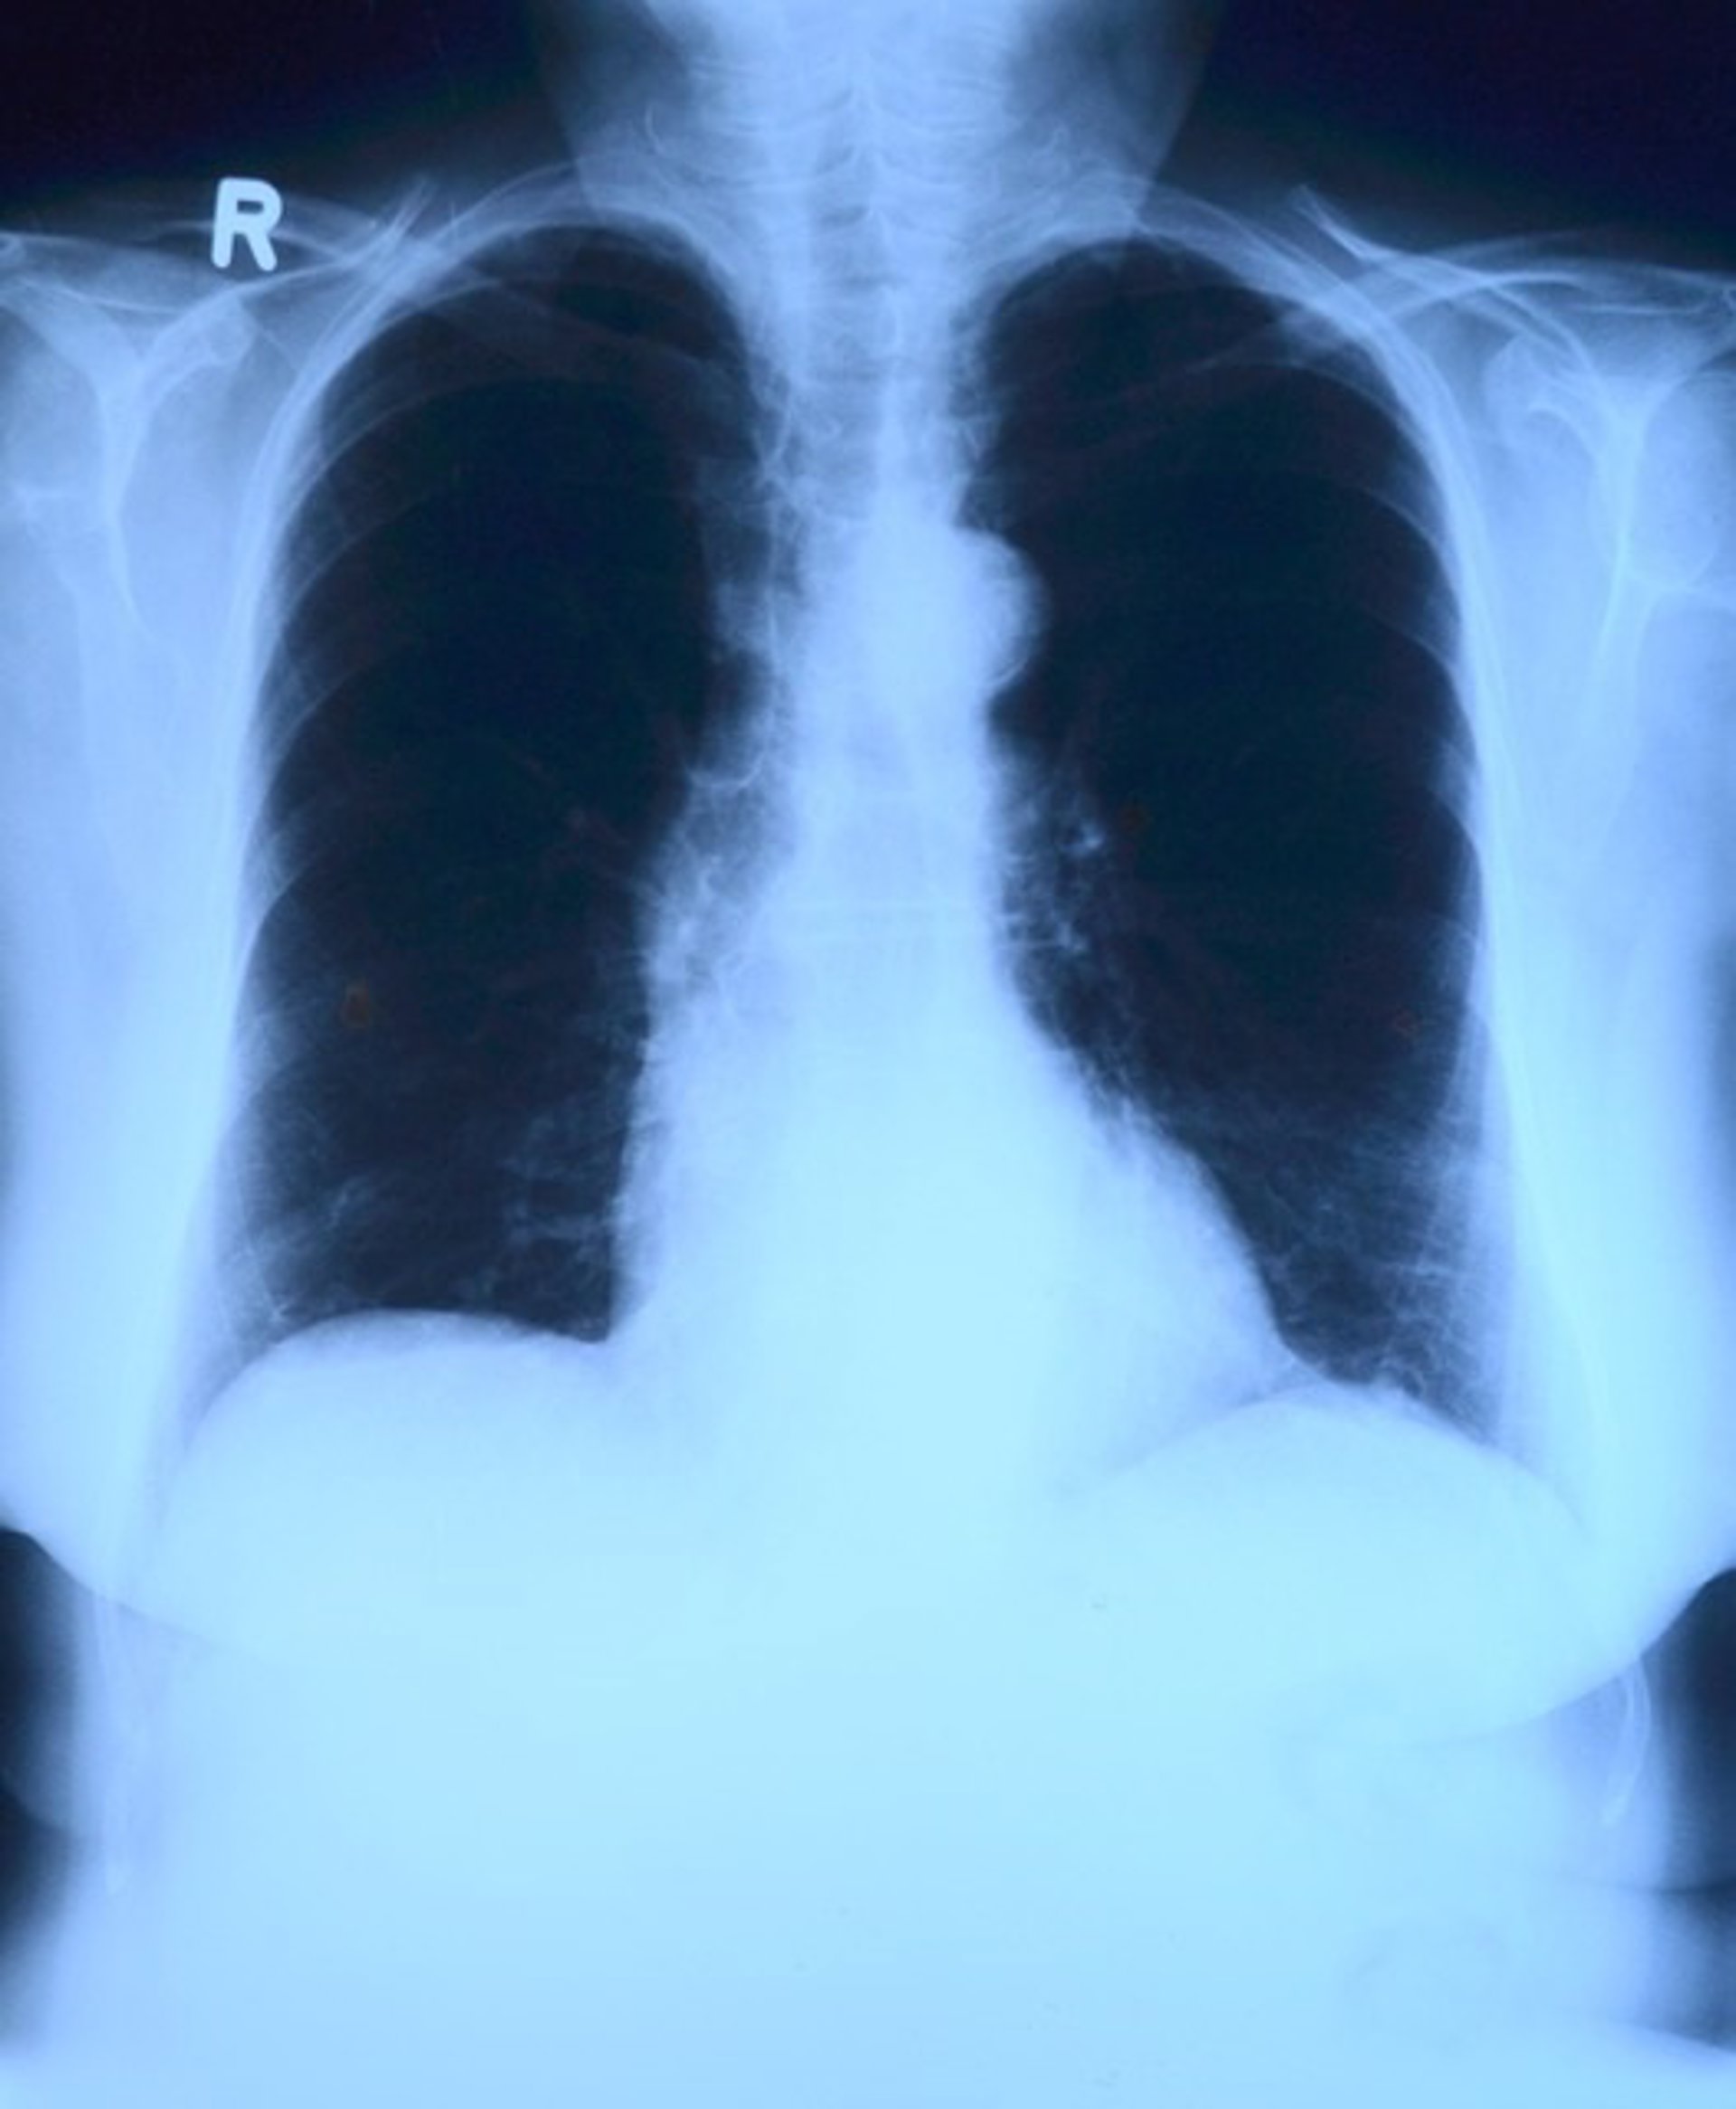

La bronquitis en la infancia predice una peor salud pulmonar en la mediana edad - PIXABAY - Archivo